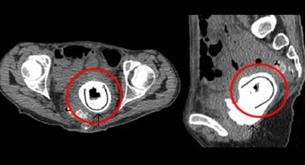

¡Encuentra un juguete sexual en su vagina diez años después!

A punto de morir por culpa de un juguete sexual anal